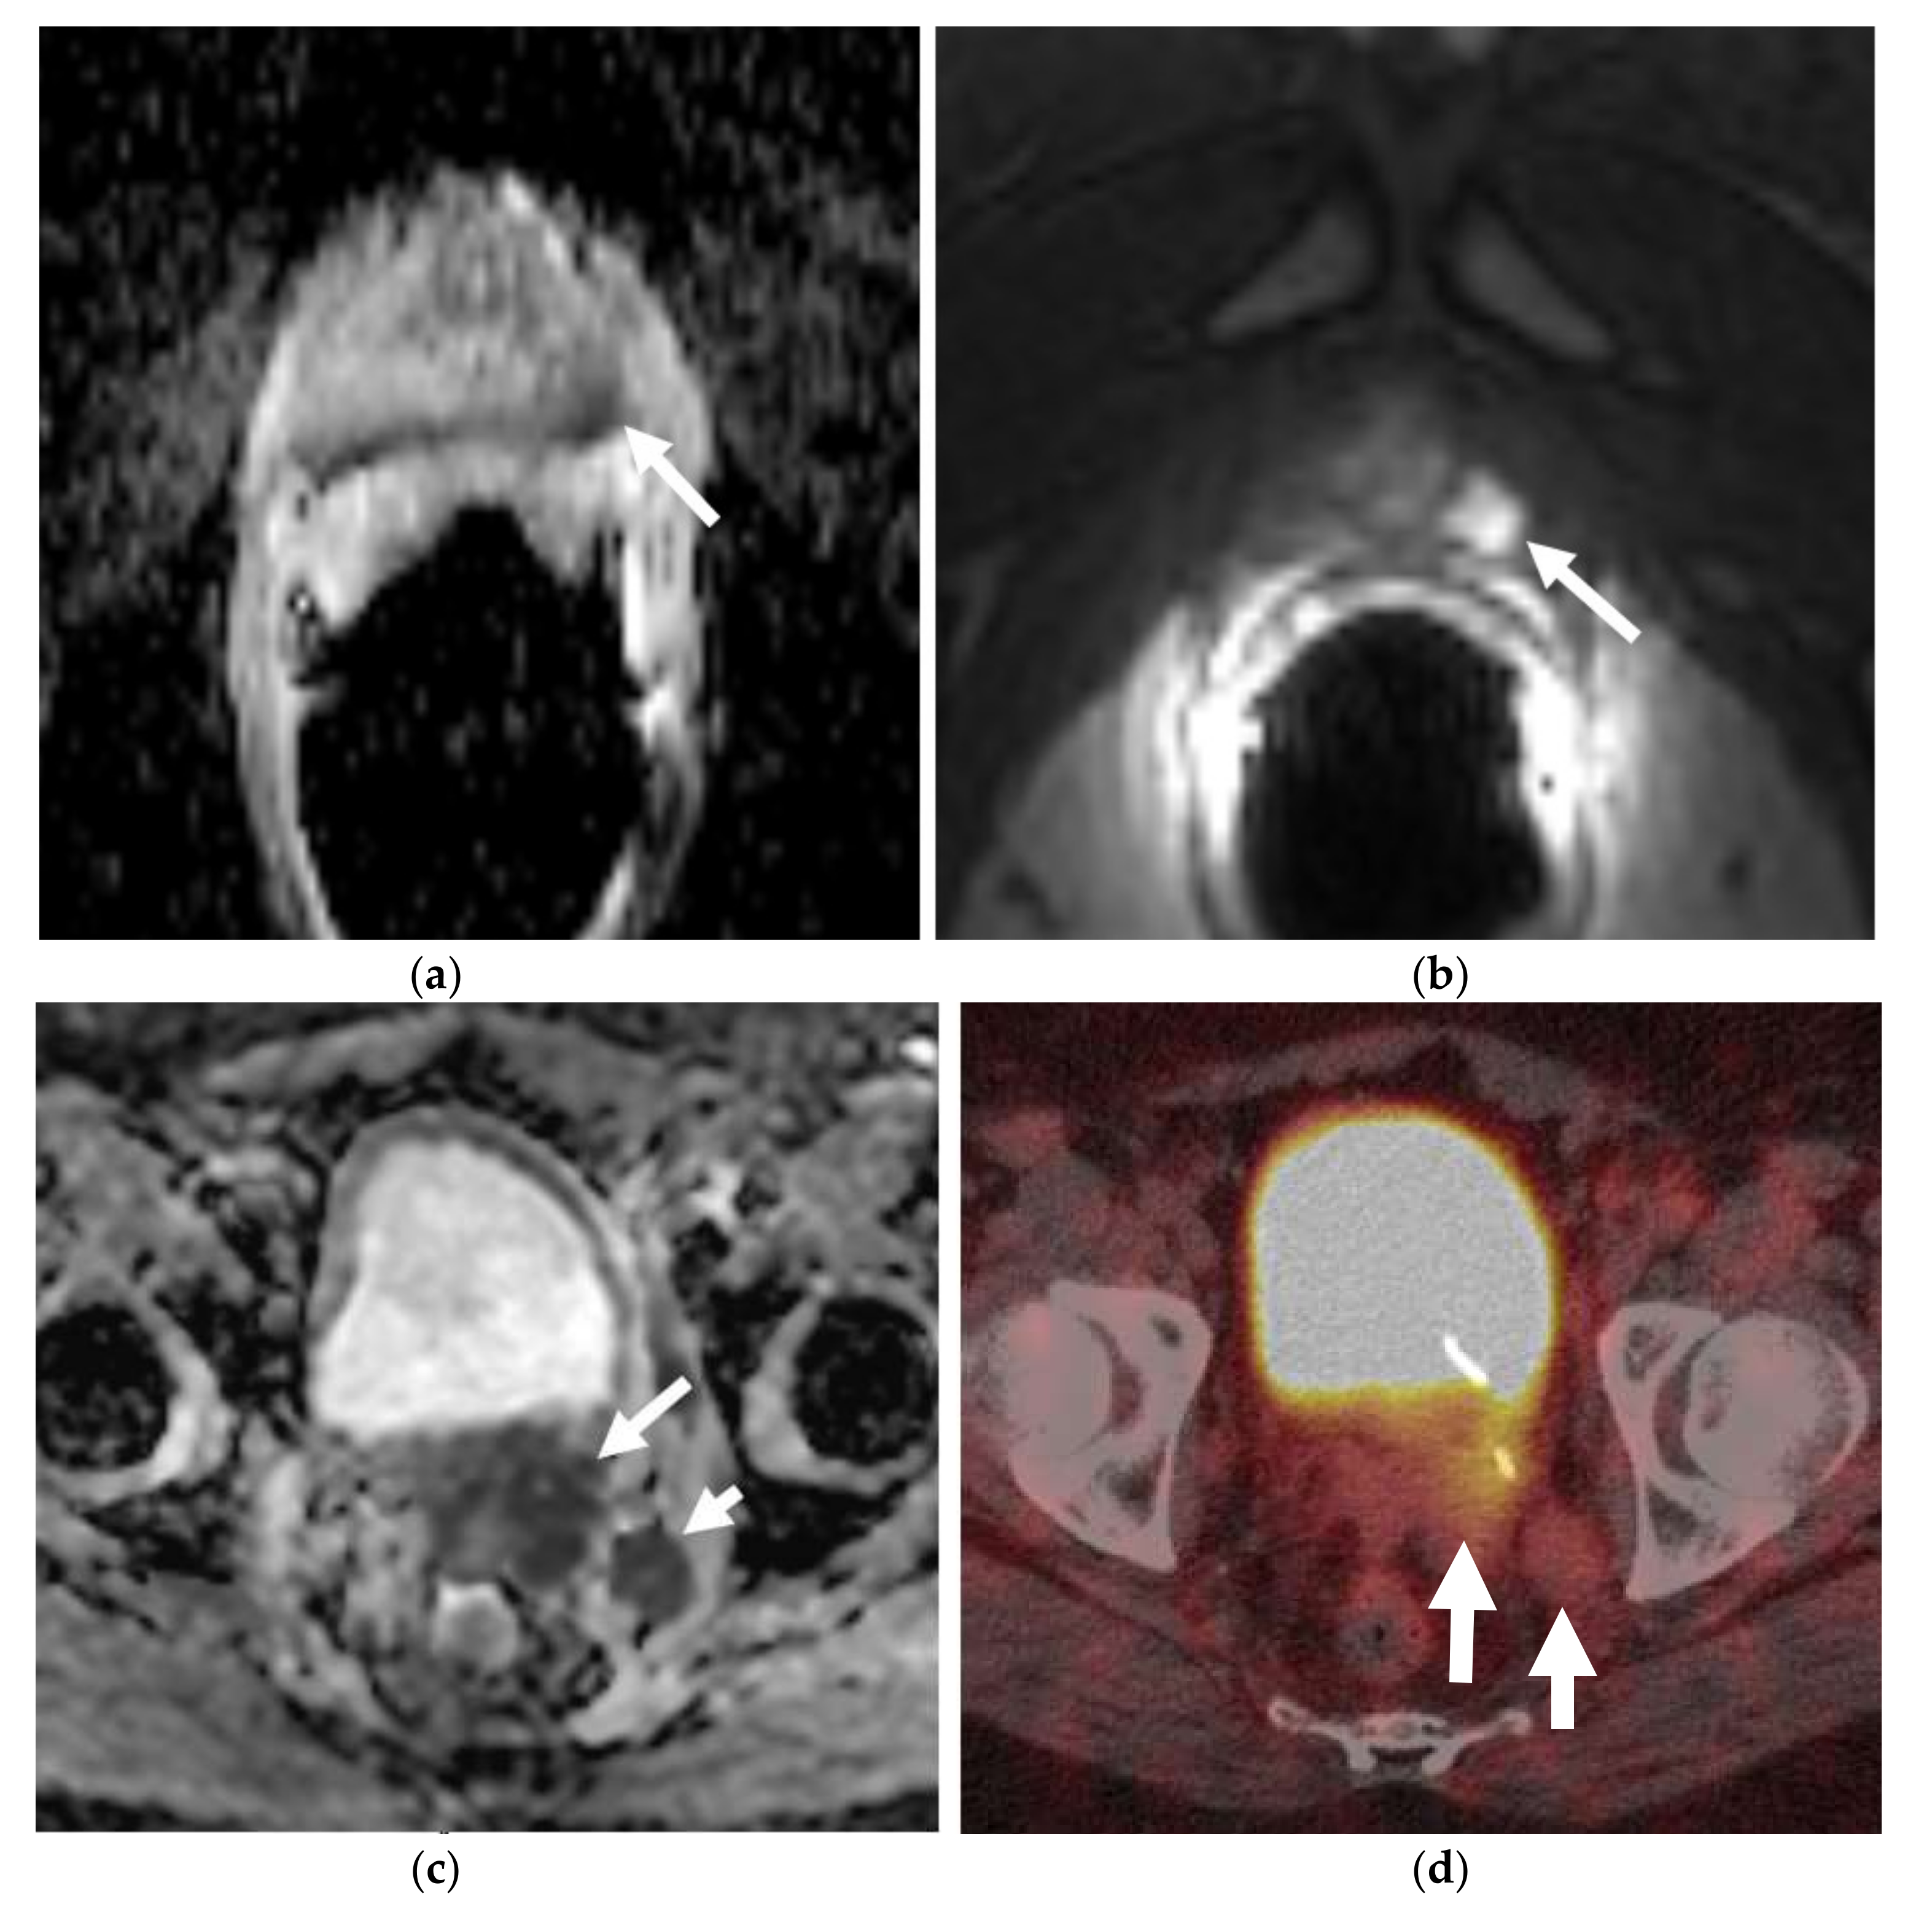

Figure 5.

An elderly patient with metastatic neuroendocrine prostate cancer. Coronal maximum intensity projection (MIP) PET image (a) and axial color fused image of 68Ga DOTANOC PET-CT (b) show intensely hypermetabolic prostatic mass (long arrow) consistent with neuroendocrine prostate cancer and hypermetabolic widespread bony metastases (short arrows). Post-treatment DOTANOC PET-CT following 4 cycles of PRRT therapy shows marked positive treatment response. There was near complete metabolic response in the bony metastases, as seen on the coronal MIP PET image (c) with minimal residual metabolic activity corresponding to some sclerotic bony metastases on axial color fused PET-CT image (d). There is also interval decrease in the extent and degree of hypermetabolic activity in the prostatic malignancy with residual activity suspicious for residual viable malignancy. Image courtesy: Divya Yadav, M.D.

2.3.2. 68 Gallium Labelled Somatostatin Analogs (68Ga-DOTATATE or 68Ga-DOTANOC)

68Ga-DOTATATE or 68Ga-DOTANOC, are 68Ga labeled somatostatin analogs that bind with high affinity to the somatostatin receptor 2 (SSTR2), which is highly expressed by NEPCs, enabling their identification by SSTR2 tracers [54,55]. 68Ga-DOTATATE or 68Ga-DOTANOC PET can be used to evaluate bony metastases and predict treatment response in these cases [54,56]. 68Ga-DOTATATE has a reported sensitivity and specificity of 82% and 90%, respectively, for detecting disease in cases of biochemically-relapsed prostate cancer [57]. This may be presumably useful in evaluation and management of low and intermediate grade neuroendocrine neoplasms, as shown in cases of gastroenteropancreatic neuroendocrine neoplasms [53,58,59]. At the same time, one should also remain aware of the false positive diagnosis in the setting of prostatitis due to inflammatory uptake [60,61] or in case of standard prostatic adenocarcinoma with inflammatory cell infiltrates [62]. Inflammatory tracer uptake usually gives rise to low- or very low-grade hypermetabolic activity and may be a clue in some of these cases [60].

From an imaging point of view, the most commonly employed imaging modalities for prostate biopsies and cancer detections are multiparametric ultrasound (US) and magnetic resonance imaging (MRI). Computed tomography (CT) is reserved for staging purposes. Thus far, conventional imaging methods cannot directly differentiate between NEPCs and prostatic adenocarcinoma; however, the presence of nodal and visceral metastases and rapid progression may suggest NEPC, which often requires histopathologic confirmation [74,75]. Various PET tracers are now available for the imaging of prostate cancer and neuroendocrine differentiation. A recent clinical case series demonstrated excellent detection rates for the metastases (95%), specifically the visceral and nodal metastases in NEPCs by using FDG-PET [51,52]. The positron-emitting somatostatin analogs, which bind to somatostatin receptors (SSRTs) with high affinity, 68 Ga-DOTATATE or 68 Ga DOTANOC are also suitable and found to be as highly accurate as the PET/CT radiotracers, for the display of somatostatin-expressing NETs [43,44]. Usmani et al. reported a case that showed the significance of somatostatin receptor scintigraphy for the detection of neuroendocrine differentiation of metastatic prostate cancer [76]. In another study of 12 patients with metastatic NEPC previously treated with ADT, 50% of the patients showed a moderate or high tracer uptake in the metastases on the 68 Ga-DOTATATE-PET/CT. Further research with higher numbers of cases is required to assess the performance of 68 Ga-Somatostatin analog-PET/CT as a new diagnostic tool for prostatic neuroendocrine neoplasms [55].

Similar to most other neuroendocrine tumors, such as small-cell lung cancer, NEPC tends to be sensitive to chemotherapy and radiotherapy. Currently, treatment of NEPCs consists mainly of prostatectomy with adjuvant platinum-based regimens. Cisplatin/carboplatin combinations with either docetaxel or etoposide, have relatively high response rates. The addition of doxorubicin to regimens has not demonstrated advantages and is associated with increased side effects [79,80,81]. In a recent study, Apostolidis et al. concluded that NEPCs can be treated similar to NETs of the gastrointestinal tract, with somatostatin analogs, everolimus, and peptide receptor radionuclide therapy (PRRT) (Figure 5) [82]. Adjuvant radiotherapy is also very important, particularly when positive surgical margins are identified [80]. Targeted therapy is an exciting new therapy for NEPCs, as early evidence suggests improved clinical outcomes. Alisertib, an agent that can inhibit the interaction between N-myc and its stabilizing factor Aurora-A, has recently entered into a phase II clinical trial. It inhibits N-myc signaling, which is a driver of NEPC progression and thus, suppresses tumor growth [83,84].